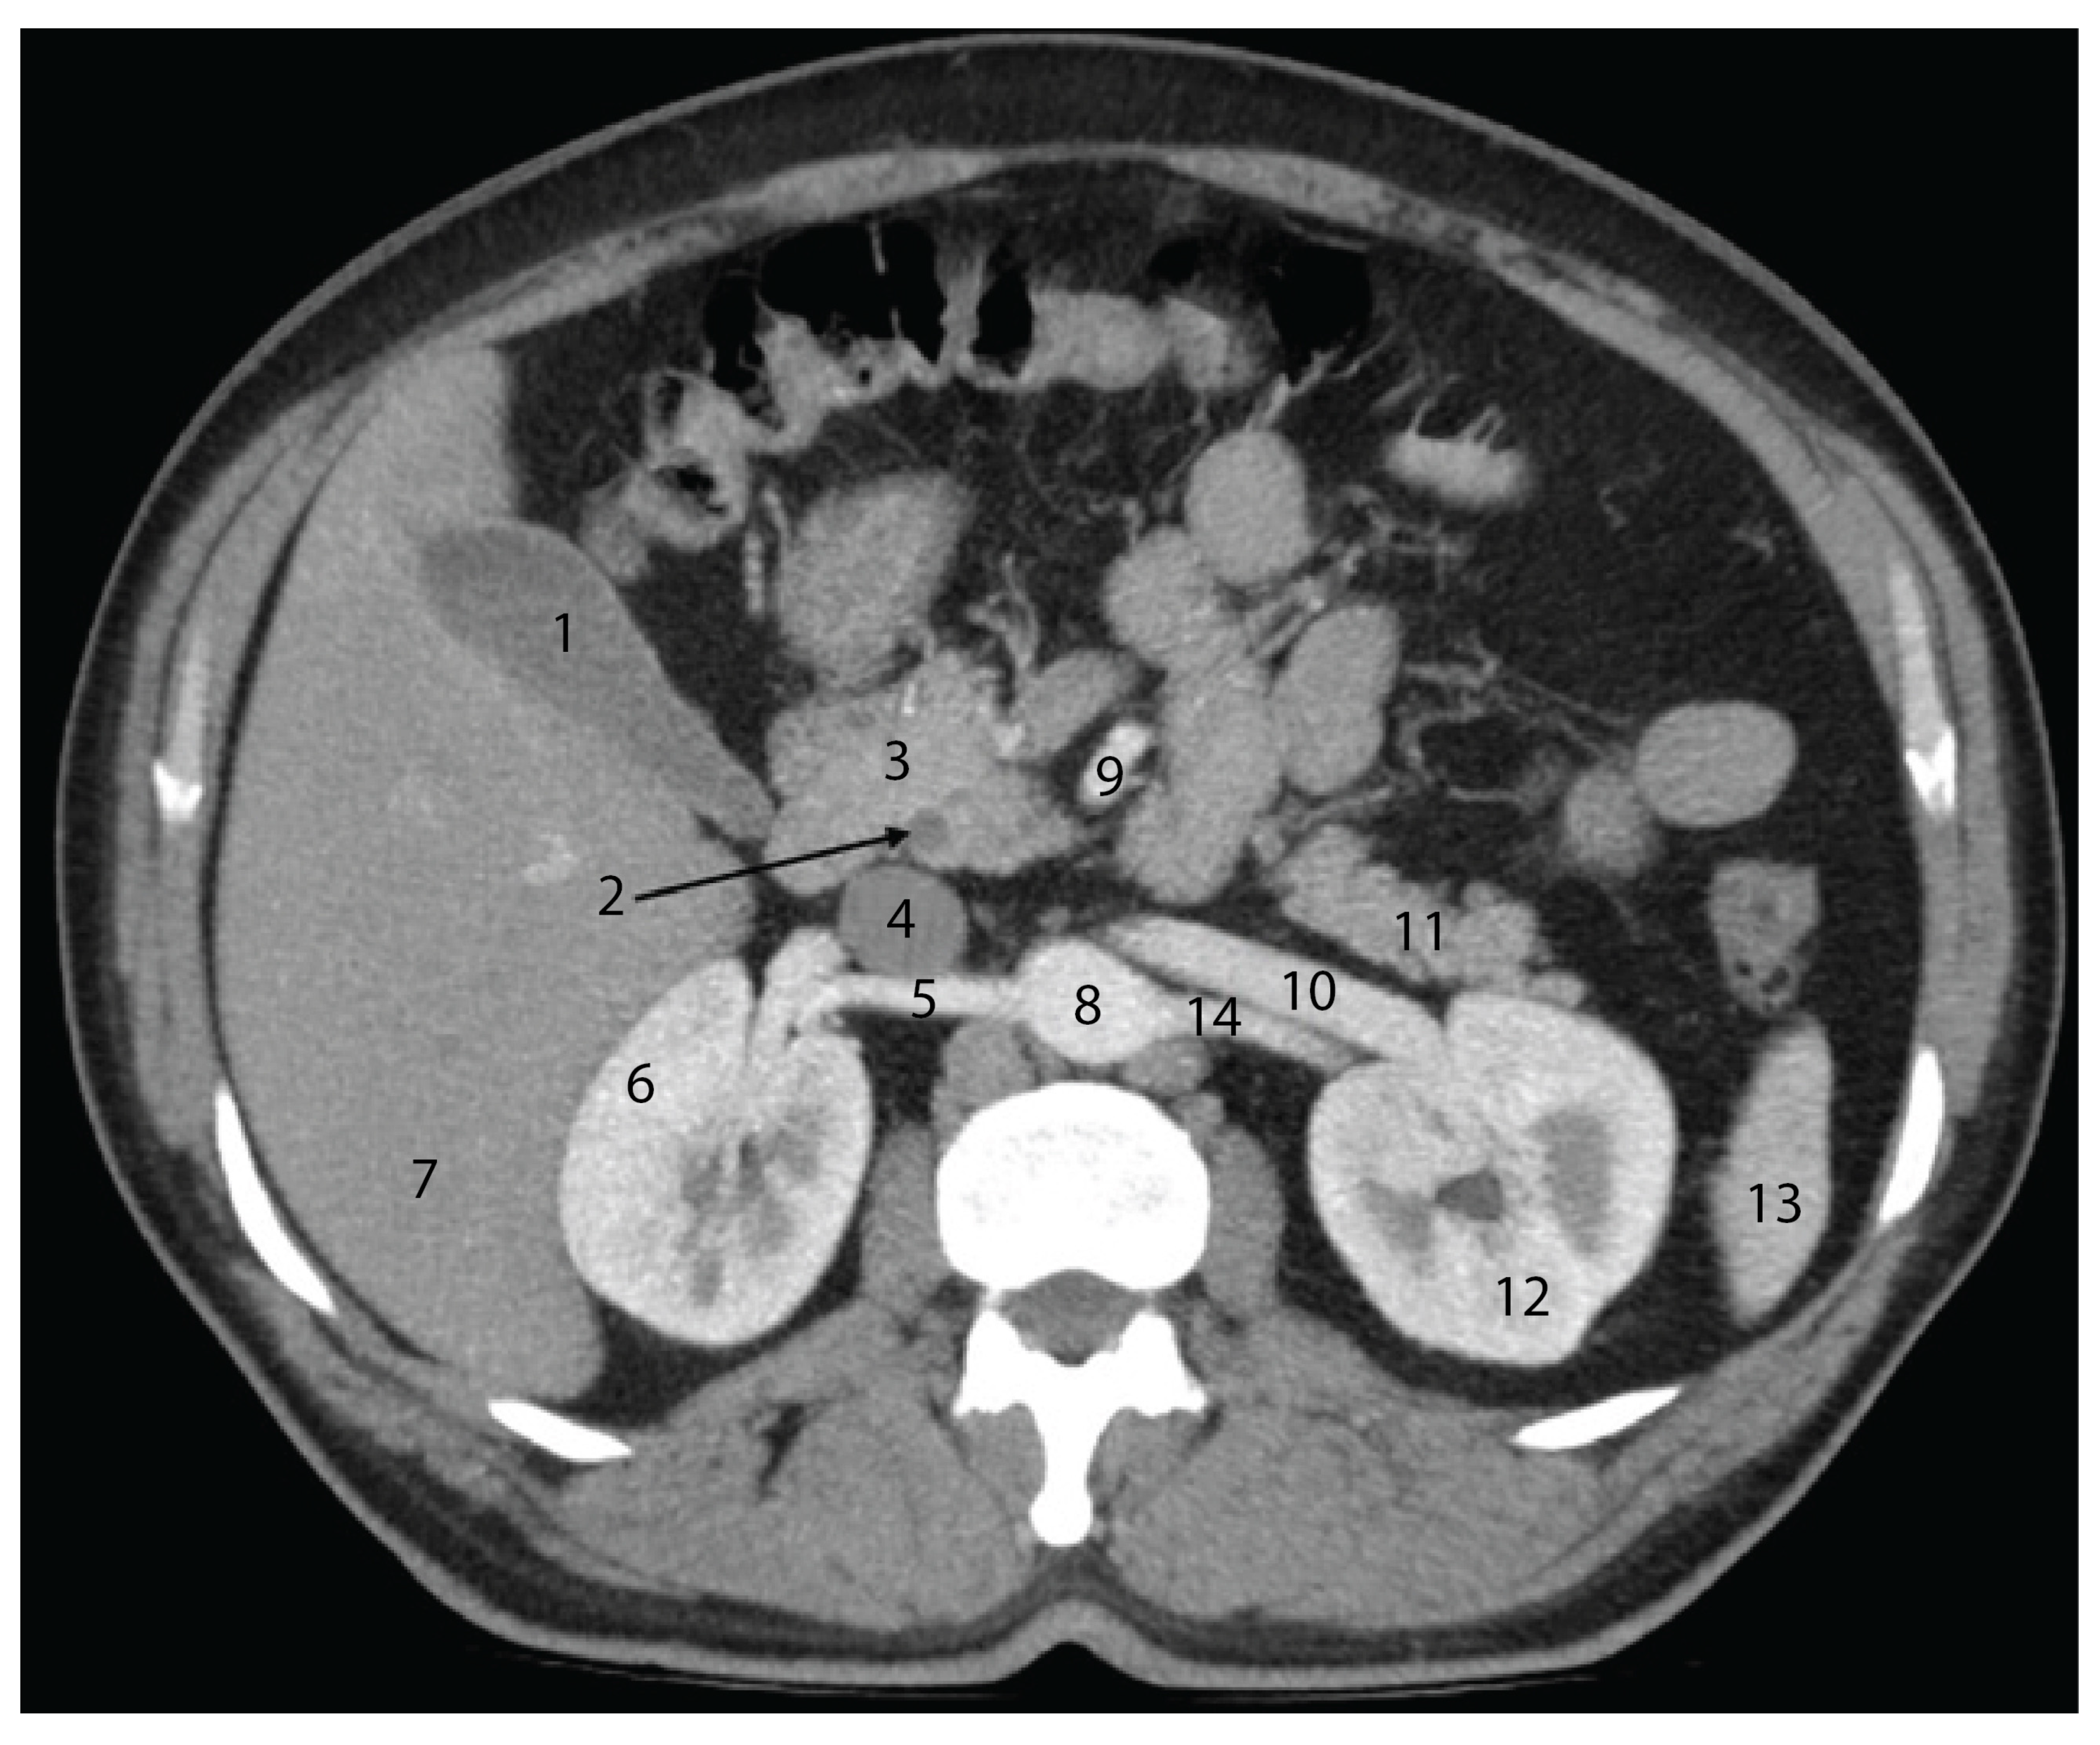

4.5. Advances in Imaging